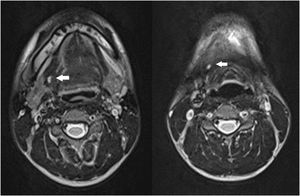

Case reportA 17-year-old boy with no other medical history presented with mucus drainage from an opening on the right side of the neck during eating or drinking, which he experienced since childhood. Physical examination revealed a 2-mm-diameter orifice near the right lateral margin of the thyroid cartilage. Mucus discharge was observed from the orifice when the patient drank water. T2-weighted MRI of the neck revealed a luminal structure up to 5 mm in diameter that extended from the right anterior neck to the right oral floor through the anteromedial side to the right submandibular gland (Fig. 1).